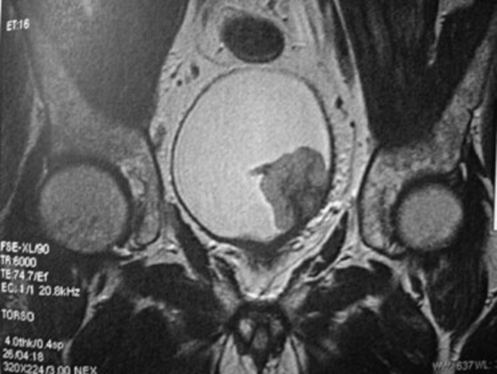

L’imagerie par résonance magnétique (IRM)

Comme l’uroscanner, l’IRM donne des renseignements sur le contenu de l’abdomen et du petit bassin.

Par contre, l’IRM n’utilise pas de rayons X mais un courant magnétique.

La visualisation des structures de l’appareil urinaire est sensibilisée par l’injection intraveineuse de Gadolinium.

Il n’est habituellement pas nécessaire de pratiquer à la fois l’uroscanner et l’uro-IRM.

Habituellement, c’est la réalisation d’un uroscanner qui est préférée dans le cadre du bilan d’extension d’un cancer de la vessie.